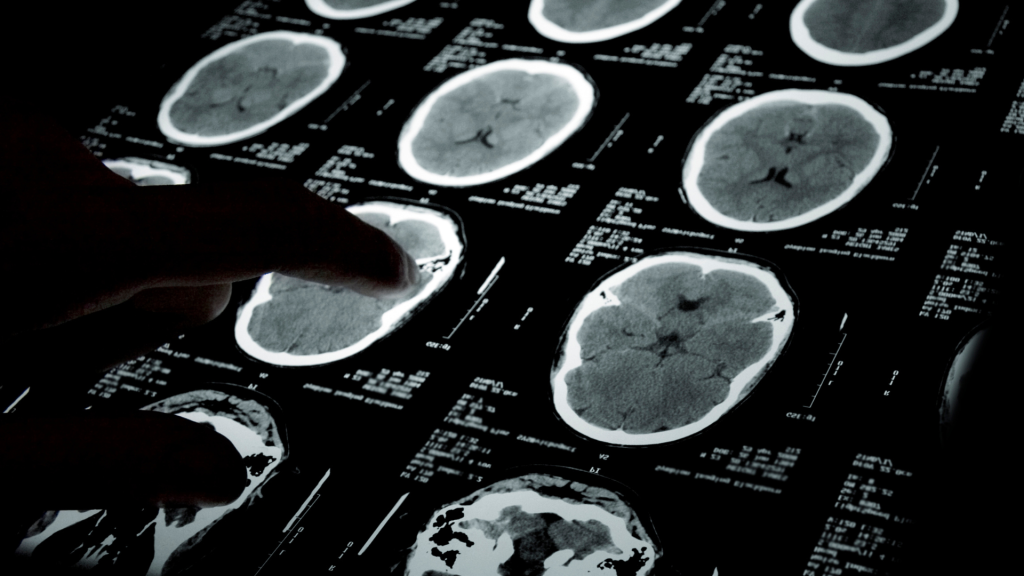

PET-CT adalah sistem hybrid yang menggabungkan pencitraan fungsi tubuh melalui PET dan pencitraan struktur melalui CT. Dalam satu scan, alat ini memberikan informasi metabolik sekaligus anatomi secara presisi. Teknologi ini sangat krusial dalam onkologi, neurologi, dan kardiologi.

Namun, data yang dihasilkan dari satu sesi PET-CT sangat kompleks. Ratusan potongan gambar dan data kuantitatif harus dianalisis oleh radiolog dalam waktu terbatas. Di sinilah AI hadir sebagai asisten cerdas yang mampu menyaring, menganalisis, dan menandai kelainan secara otomatis.

Dengan algoritma pembelajaran mesin, AI dapat memproses citra PET-CT lebih cepat dibanding manusia. AI mampu mengenali pola metabolik abnormal, mengukur intensitas tracer, dan bahkan membandingkan hasil dengan data klinis sebelumnya. Proses yang memakan waktu puluhan menit kini bisa berlangsung dalam hitungan detik.